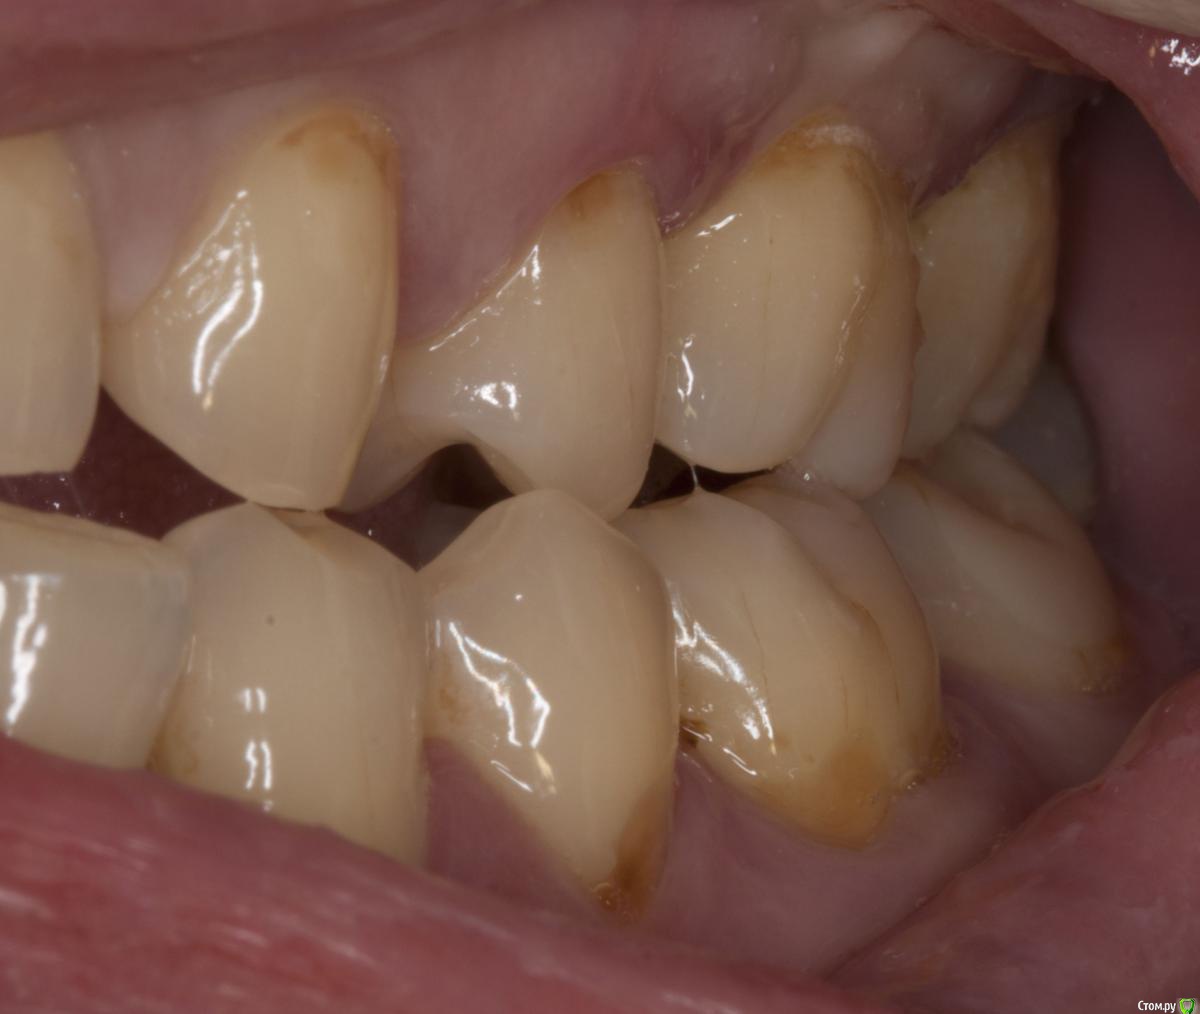

DmitrySH Опубликовано 28 июля, 2015 Поделиться Опубликовано 28 июля, 2015 (изменено) Такой вот сюрприз от знакомого, у которого на весь рот пара пломб да одна коронка. С гигиеной только плохо, как я с ним не боролся. Не могу понять этиологию. http://s008.radikal.ru/i303/1507/f8/dcbbdfee70a4.jpg Изменено 28 июля, 2015 пользователем dmitrySH Ссылка на комментарий

DmitrySH Опубликовано 28 июля, 2015 Автор Поделиться Опубликовано 28 июля, 2015 Визуально кариеса нет. Пациент из той группы, у которой зубы могут быть покрыты кучей налета, все желтого цвета, но кариесу мало подвержены.КТ делал, хотел понять что с костью вокруг зуба, что с пазухой. Небно абсцесс, все мягкое, отечное. Изначально думал, что только пародонтальная проблема. С гайморитом отдельно надо разбираться, с другой стороны в пазухе вообще просвета нет. Ссылка на комментарий

Sampson Опубликовано 29 июля, 2015 Поделиться Опубликовано 29 июля, 2015 (изменено) Зуб на удаление и диагностическое вскрытие. Пациент к ЛОРуФото зуба хочется увидеть. Пульпит может быть следствием пародонтита из-за оголения боковых ответвлений. Изменено 29 июля, 2015 пользователем Sampson Ссылка на комментарий

DmitrySH Опубликовано 29 июля, 2015 Автор Поделиться Опубликовано 29 июля, 2015 (изменено) Небно зондируется до апекса, на холод не реагирует, впрочем и перкуссия тоже отрицательна. Болит только слизистая небно. Сейчас пообщался, после вчерашней ревизии "кармана" все прошло, ничего не болит. Он в субботу еще в отпуск собрался Изменено 29 июля, 2015 пользователем dmitrySH Ссылка на комментарий

M@estro Опубликовано 29 июля, 2015 Поделиться Опубликовано 29 июля, 2015 (изменено) Травматический узел. Изменено 29 июля, 2015 пользователем M@estro 10 Ссылка на комментарий

M@estro Опубликовано 3 августа, 2015 Поделиться Опубликовано 3 августа, 2015 но у вашем случае у антагониста пломба, а у паца тс нет пломбы на антагонисте. или там другая причина супраоклюзии? Я специально сделал серию фото, чтобы виден был перегруз 2.6 при левой латеротрузии. Ссылка на комментарий